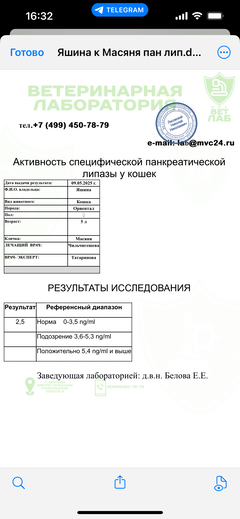

Была куплена в питомнике взрослой. У Масяни начались проблемы с кишечником и она стала подтекать и все пачкать. Надо отдать должное хозяевам - ее обследовали вдоль и поперек - как говорили местные врачи, сдавали много анализов но диагноза так и не поставили.

Ярко выраженная болезненность в области крестца, на обезболе полегче. По результатам приема невролога проведена миелография - множественная компрессия, возможно опухоль, возможно грыжа, нужно удалять...